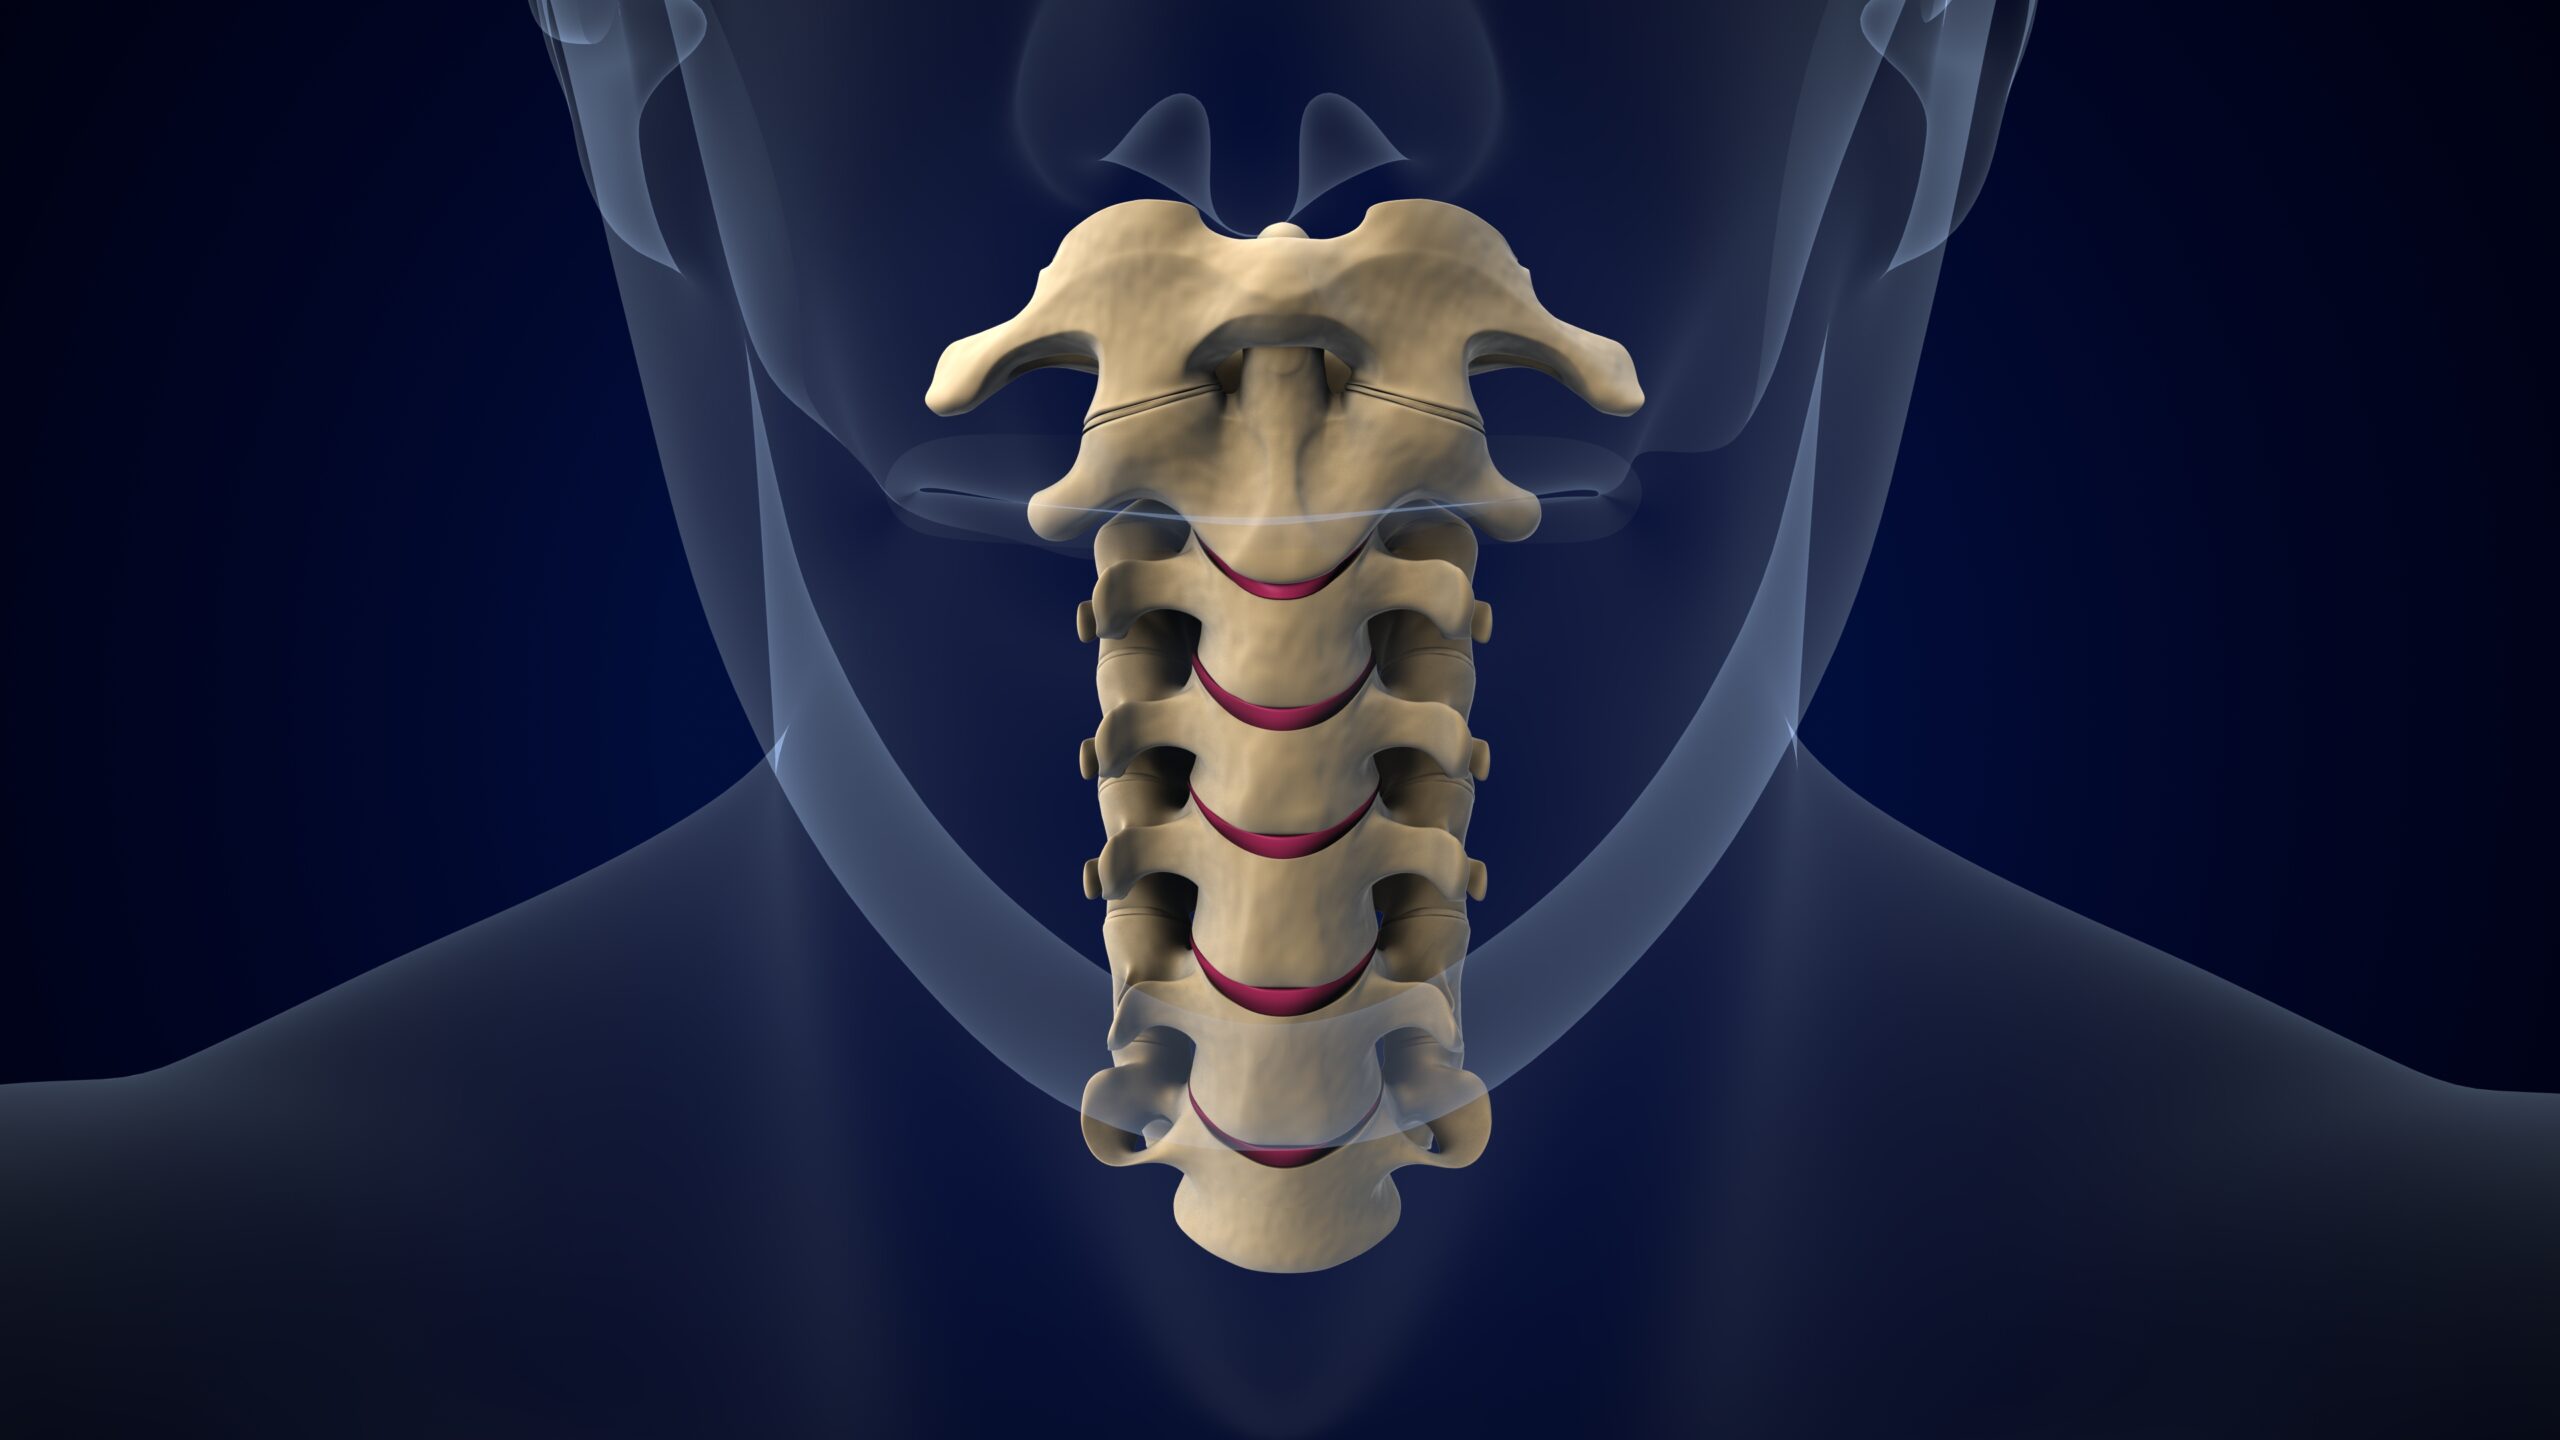

Anterior Cervical Discectomy and Fusion (ACDF): A Trusted Surgical Solution for Neck Pain and Nerve Compression

Persistent neck pain, arm numbness, or weakness in the upper limbs can significantly impair your daily life. When these symptoms are caused by a herniated disc or cervical spine degeneration that doesn’t respond to conservative treatment, surgical intervention becomes necessary. One of the most commonly performed and successful procedures for cervical spine issues is Anterior Cervical Discectomy and Fusion (ACDF).

What Is ACDF?

Anterior Cervical Discectomy and Fusion (ACDF) is a surgical procedure that removes a damaged or herniated disc from the cervical (neck) spine through an incision in the front (anterior) of the neck. After the problematic disc is removed, the empty disc space is filled with a bone graft or an artificial spacer, and the vertebrae are fused together using a plate and screws. The goal is to stabilize the spine and relieve pressure on the spinal cord or nerve roots.

This procedure is especially effective in treating:

- Herniated cervical discs

- Cervical degenerative disc disease

- Spinal stenosis

- Cervical spondylotic myelopathy

- Cervical radiculopathy (pinched nerves)